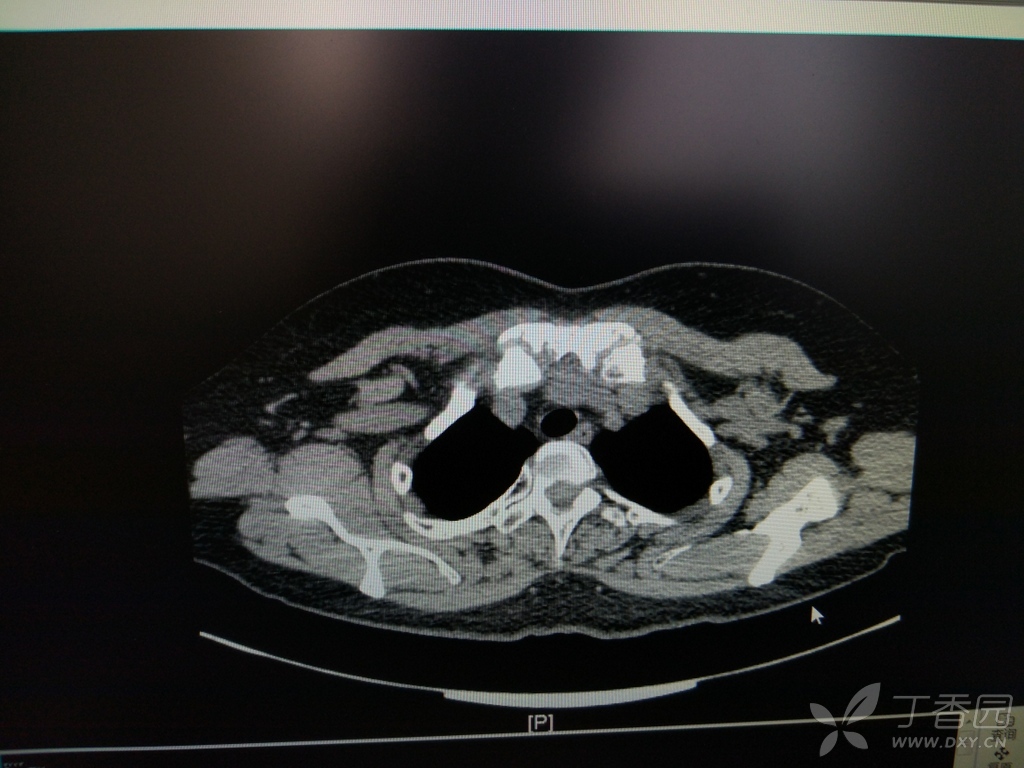

女性,54岁,胸骨柄突起畸形数年,偶尔疼痛

胸锁关节,胸骨柄区病变影像诊断专题讨论 [精华]